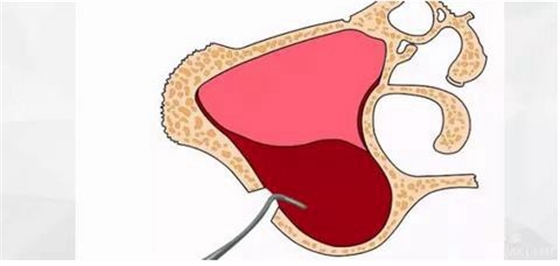

首先使用開孔鉆刺穿上頜竇頰側(cè)骨壁。

水壓將頰側(cè)上頜竇膜剝離。